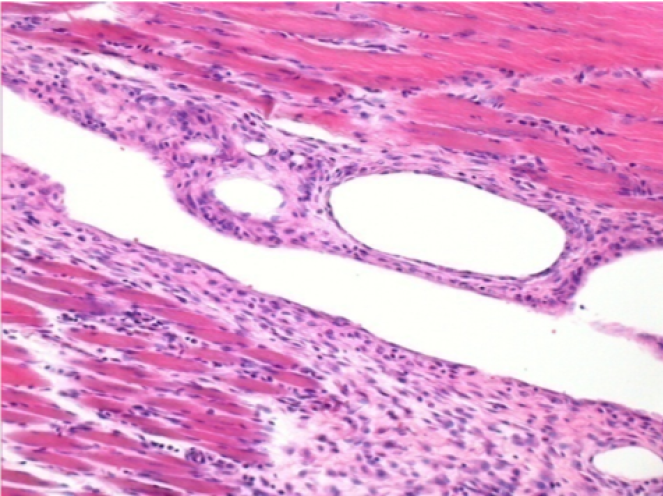

Iniezione Endopeel nel tessuto subcutaneo SC

Scatola 6

0.5 ml ( 5x 0.1ml): Iniezione SC di Endopeel nel tessuto pretibiale subcutaneo SC destro (Dx).

Sx:200x-Controllo-SC

Dx-Giorno10-SC-200X

Dx-Giorno30-SC-200X

Dx-Giorno90-SC-200X

Dx-Giorno210-SC-200X

Dx-Giorno210-SC-400X

Endopeel induce una miofibrolisi selettiva reversibile e una risposta infiammatoria approssimativamente nel periodo di 1 mese.

I cambiamenti dei tessuti muscolari sono quasi completamente reversibili.

Il muscolo é il posto migliore per iniettare Endopeel ,per la sua maggiore efficacità, il controllo e la durata della sua azione.

Nessuna necrosi ne ascesso sono stati osservati durante la sperimentazione.